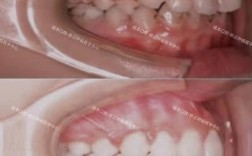

深覆合是口腔正畸中常见的错颌畸形类型,主要表现为上前牙切缘盖过下前牙牙冠过多,垂直距离过小,可能伴随下颌后缩、面部比例不协调等问题,长期存在可能导致咬合创伤、颞下颌关节紊乱甚至消化功能异常,其矫正过程需结合患者年龄、错颌程度、骨骼条件等因素综合设计,通常需经历术前评估、方案设计、主动矫正、保持巩固四个阶段,每个阶段环环相扣,以确保矫正效果稳定且兼顾功能与美观。

根据检查结果,医生会综合评估患者的骨骼型、牙型、年龄及美观需求,确定矫正目标(如解除深覆合、排齐牙齿、建立正常咬合关系、改善面部侧貌),并选择合适的矫正方法,青少年患者(生长发育期)若为骨性深覆合,可能配合前方牵引、头帽颏兜等生长改良治疗,引导下颌向前或抑制上颌发育;成人骨性深覆合则常需正畸-正颌联合治疗,针对牙性深覆合,方案设计需重点解决Spee曲线过深问题,常用方法包括:

这是矫正深覆合的核心阶段,重点通过“压低上前牙、伸长下前牙、调整颌平面”三方面改善垂直距离。